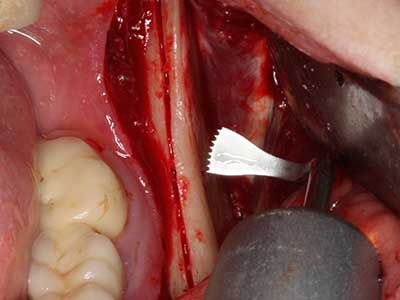

En la extracción de bloques óseos la piezocirugía también presenta ventajas adicionales: Además de la alta precisión en la osteotomía que ya se ha descrito antes, se ha comprobado que el uso de los delgados insertos de sierra resulta especialmente cuidadosas con el hueso. Frente a esto, sobre todo cuando se usan las fresas de Lindemann, cabe esperar pérdidas en la extracción significativamente más altas debido al mayor grosor de la parte frontal del cabezal (Lakshmiganthan, Gokulanathan et al. 2012). La separación basal que se necesita en particular en los injertos de bloque extraídos de forma retromolar se ve facilitada mediante sierras perpendiculares especialmente previstas a tal fin, lo que permite considerar que la cirugía piezoeléctrica es un procedimiento preciso y seguro para la obtención de bloques de hueso en el área retromolar (Happe 2007) (fig. 1-12).

El tejido óseo no solo tiene un contenido puramente mineral, sino que también presenta una importante proporción de fibras de colágeno. Esto no solo garantiza una buena resistencia a la presión, sino también una cierta flexibilidad, que puede aprovecharse para la realización de aumentos. En la plastia de expansión clásica a efectos de una partición ósea, la cresta maxilar atrofiada se divide en su eje longitudinal y, tras alcanzar una profundidad de osteotomía suficiente, se extiende con cuidado (fig. 13-16), en un caso ideal sin desperiostizar de forma visible el maxilar (Brugnami, Caiazzo et al. 2014, Stricker, Fleiner et al. 2014). Los sistemas de tornillos y placas con distancia de expansión creciente han demostrado su eficacia para distanciar entre sí las dos tablas óseas por debajo del umbral de rotura. Por regla general, se requieren anchuras de hueso residual de al menos 3 a 4 mm (Chiapasco, Zaniboni et al. 2006) para garantizar una flexibilidad y una cobertura ósea suficientes de los implantes que van a incorporarse. En caso necesario, una osteotomía de descarga vertical unilateral o bilateral puede mejorar la flexibilidad. Como alternativa a la técnica clásica se ha descrito una combinación con otras técnicas de aumento, sobre todo en la parte bucal.

Con el uso de sierras piezoeléctricas la división se efectúa de forma especialmente cuidadosa y sin pérdidas importantes de las dimensiones, por lo que no se han encontrado diferencias significativas entre los implantes realizados en el maxilar dividido y en la cresta alveolar no deficitaria (Chiapasco, Zaniboni et al. 2006, Danza, Guidi et al. 2009). No obstante, precisamente en la partición profunda y limitada de forma local, es preciso asegurarse de que exista una adecuada irrigación por agua para evitar que se produzcan sobrecargas térmicas en las áreas de osteotomía apical.